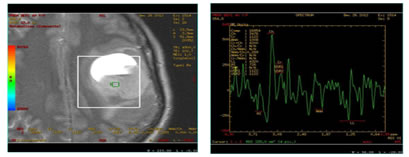

Figure 1: 40 year old lady with left parieto-temporal GBM showing necrosis and high choline peak on MR Spectroscopy